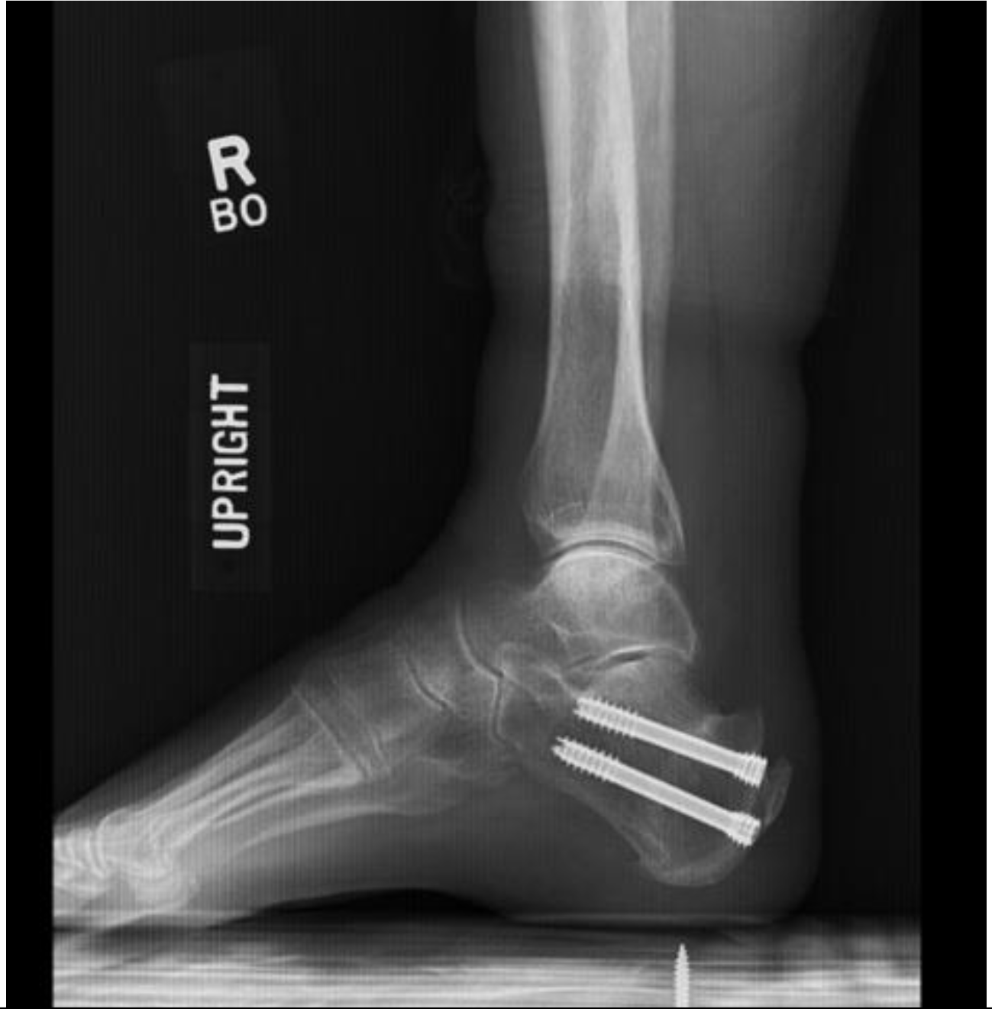

Fig. 3

Postoperative lateral radiograph demonstrating two posterior screws and correction of Haglund’s deformity